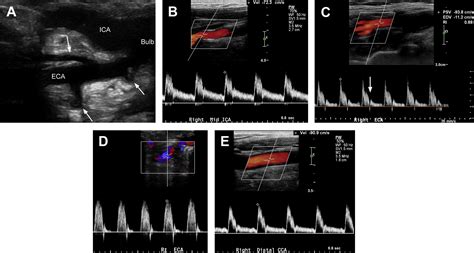

A Carotid Artery Scan, also known as a carotid ultrasound, is a diagnostic test that uses sound waves to create images of the carotid arteries. This procedure helps healthcare providers detect any blockages, narrowing, or other abnormalities in the arteries that could lead to serious health issues. The scan is painless and typically takes about 20-30 minutes to complete.

• Preparation: The patient is usually asked to lie on an examination table. A gel is applied to the neck area to improve the transmission of sound waves.

• Ultrasound Probe: A technician or healthcare provider uses a handheld device called a transducer to emit sound waves into the neck. The transducer is moved along the neck to capture images of the carotid arteries from different angles.

• Image Capture: The sound waves bounce off the arteries and create echoes that are converted into images on a computer screen. These images show the structure and blood flow within the arteries.

• Analysis: The images are analyzed by a radiologist or vascular specialist who looks for any signs of plaque buildup, narrowing, or other abnormalities.

During the Carotid Artery Scan, the patient will lie on an examination table while a technician applies a gel to the neck and uses a transducer to capture images of the carotid arteries. The procedure is painless and typically takes about 20-30 minutes. After the scan, the patient can resume normal activities immediately.

Following the scan, the images are analyzed by a radiologist or vascular specialist. The results are usually available within a few days, and the healthcare provider will discuss the findings and any necessary follow-up steps with the patient.